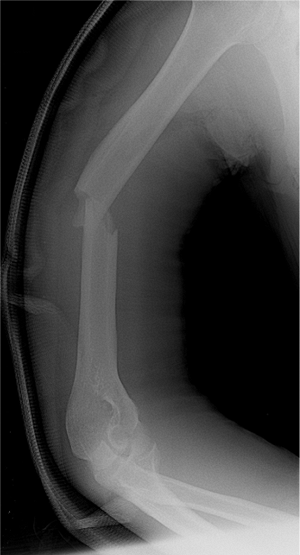

lateral views of the entire humerus. Because the arm should not be

manually rotated through the fracture site in an attempt to obtain a

lateral view, a transthoracic lateral is the preferred view. The

diameter of the medullary canal size, canal length, and anterior

deviation of the distal canal are measured on the lateral radiograph (4).

alignment of the humeral canal and the entry portal (Fig. 6.1) (4).

a coaptation splint and sling (Fig. 6.2). The

Figure 6.2. Preoperative radiograph of a diaphyseal fracture of the humerus.